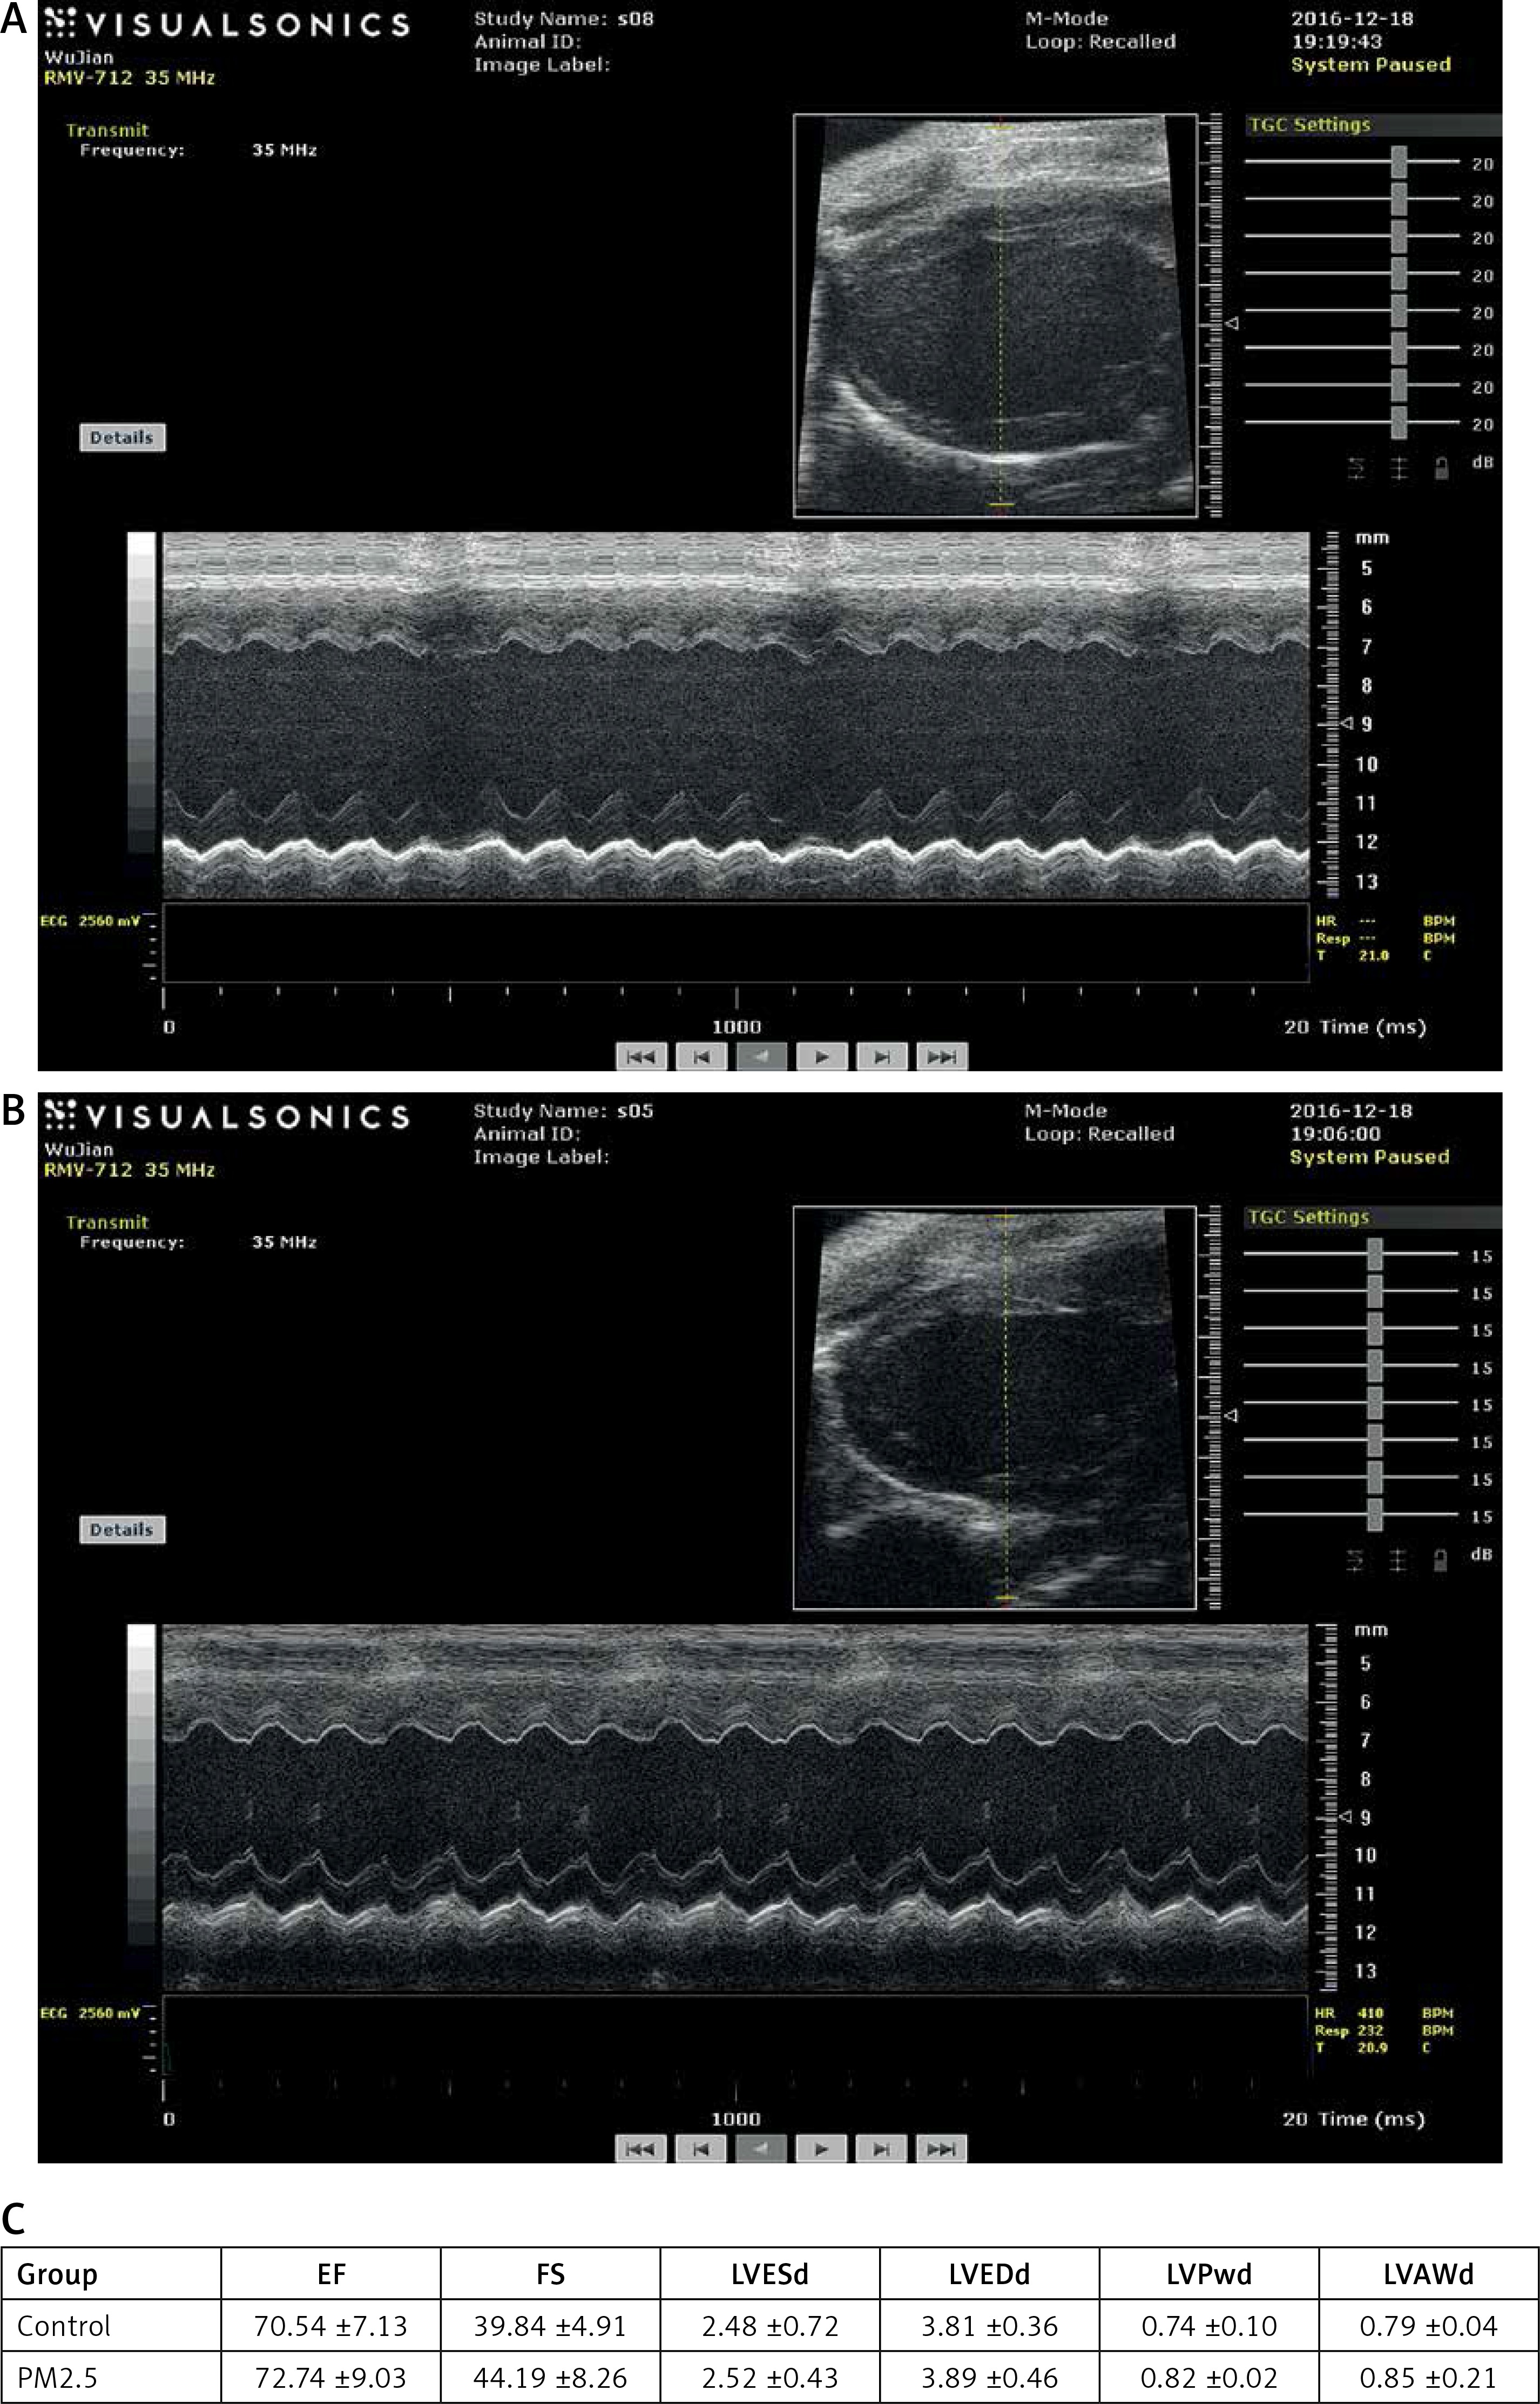

PM2.5 failed to affect cardiac function as measured by echocardiography

Quantitative analysis indicated that there were no differences in LVEDd and LVESd and no differences in LVAWd and LVESd between the groups, suggesting that PM2.5 did not affect the degree of myocardial hypertrophy, and the remaining indices were similar to those of control mice. All data are shown in Figure 6 (Tables III, IV).

Figure 6

PM2.5 failed to affect cardiac function tested by echocardiographic images in apoE–/– mice. A – Representative control group apoE–/– mice, heart structure; B – representative PM2.5 group, mice exposed to 30 mg/kg/day, LVAW and LVPW showed no significant difference compared to control mice. Data are shown in Figure 6 C